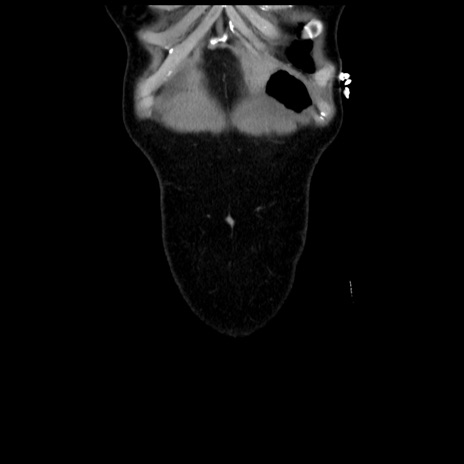

矢状断像

【症例】 50歳代女性

【主訴】 腹痛

【現病歴】前日生レバーを食べた。今朝に排便あり。 昼前に突然発症の腹痛を生じ、当院救急外来を受診した。

【既往歴】 子宮筋腫にてで子宮全摘後

【身体所見】 意識清明、腹部:平坦、軟、下腹部やや左を中心に圧痛・反跳痛あり、筋性防御あり

【データ】WBC 7800、CRP 0.07